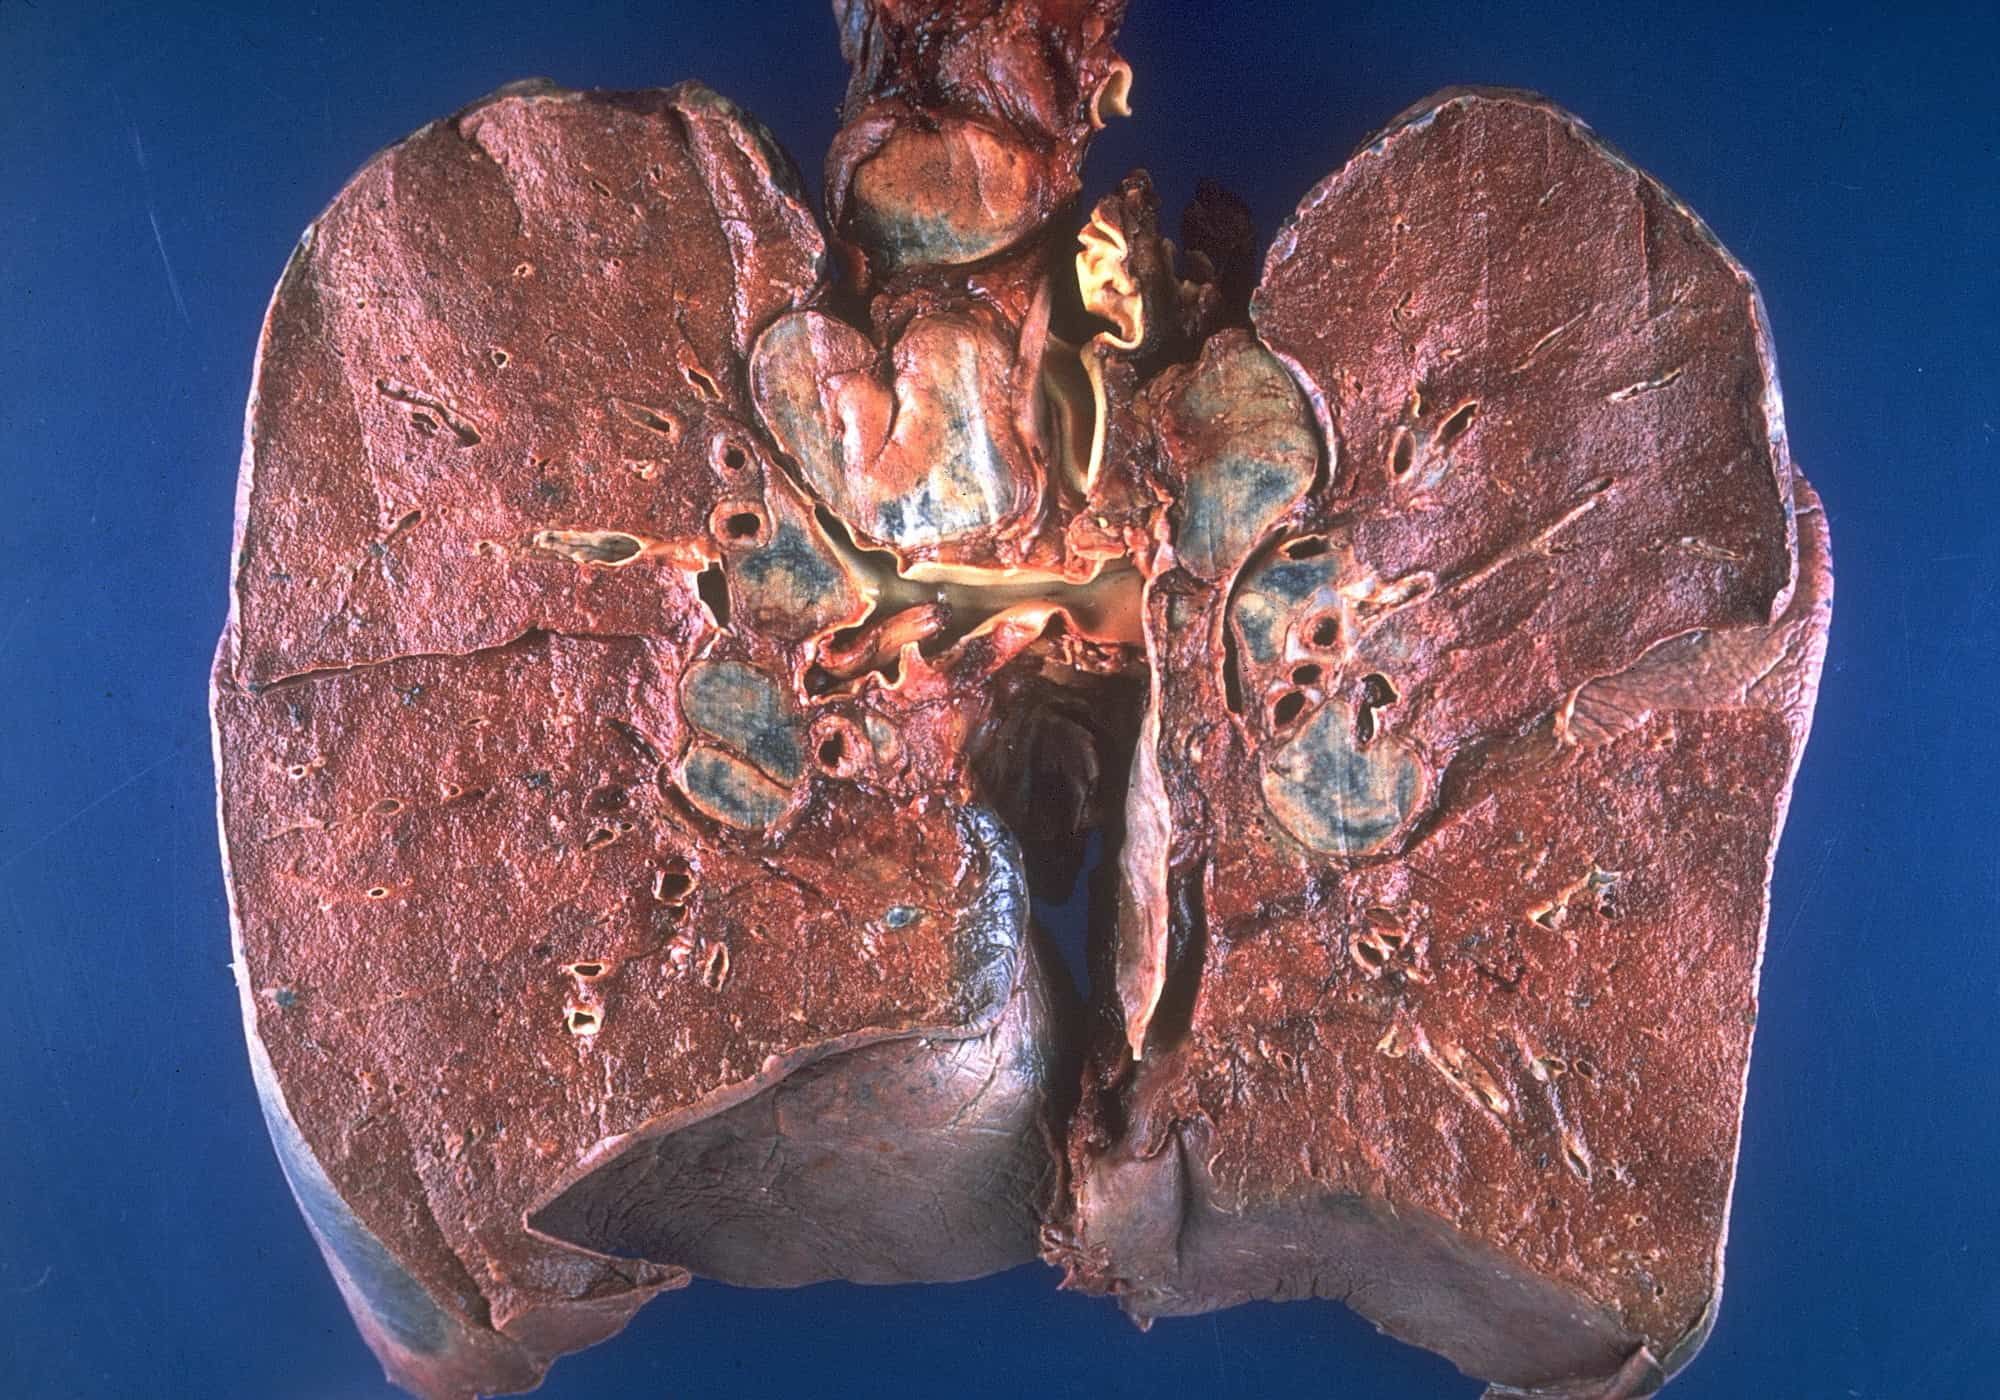

Bệnh phổi là gì?

Bệnh phổi chỉ các cơn rối loạn ảnh hưởng đến phổi, cơ quan giúp chúng ta thở. Vấn đề hô hấp do bệnh phổi gây ra có thể dẫn đến tình trạng không cung cấp đủ oxy cho cơ thể. Các ví dụ về bệnh phổi là:

Phổi là một phần của hệ cơ quan phức tạp, nở rộng và xẹp lai hàng ngàn lần mỗi ngày để hấp thu oxy cho cơ thể và thải carbon dioxide. Bệnh phổi có thể xảy ra nếu bất kỳ phần nào trong hệ hô hấp gặp vấn đề. Bệnh phổi là một trong số những bệnh thường gặp nhất trên thế giới.